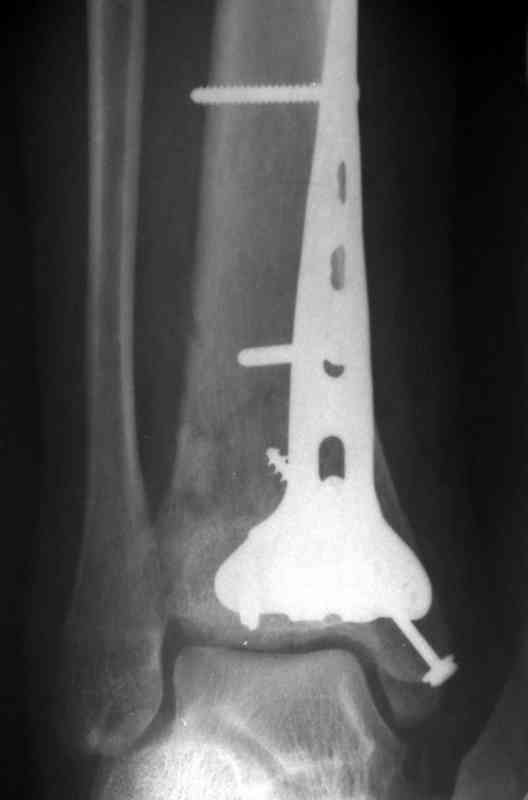

Послала ещё два снимка, если не пройдут, пошлю ещё. Дрягин. Если есть вопросы, готов ответить.